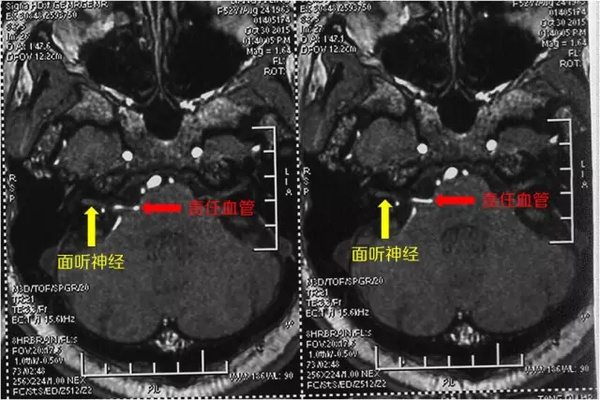

我们可以看见,这根血管和面神经紧密接触,刺激面神经不断放电

插播一个张医生小课堂 责任血管是什么意思?

责任血管是我们医学中使用的术语,就是指这个血管是引起病变的原因。比如在面肌痉挛中,某根小血管压迫到了面神经,引起面肌痉挛,那么这根血管就叫做责任血管

我们再来看这一幅图,这是磁共振检查发现的,有一根小血管压迫(红色箭头所指的白色高亮条状影)压迫到了面神经